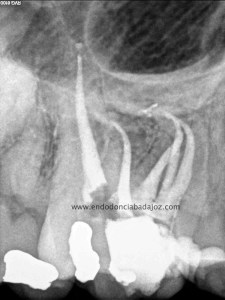

El sistema de obturación que usamos fue condensación vertical por ola de continua:

(down pack)

Hicimos el backfilling con la pistola Obtura II: